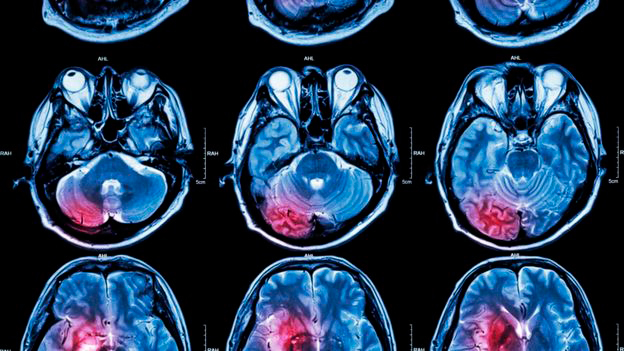

Esta investigación, publicada en la revista «Human Physiology», indicó que el cerebro masculino requiere de más esfuerzo y tiempo para cambiar de tarea, a diferencia de las mujeres, según informa ABC.

«Nuestros estudios sugieren que es más fácil para las mujeres cambiar su foco de atención en cuanto a las tareas que realizan y no necesitan el uso de otros recursos adicionales, a diferencia de los hombres», explicó la neuropsicóloga y una de las responsables del estudio, Svetlana Kuptsova.

Acorde a los resultados postulados, los hombres entre 20 y 50 años necesitan consumir más energía para cambiar de tarea, en comparación a las mujeres de la misma edad. Despues de los 50 años, esta diferencia comienza a disminuir.